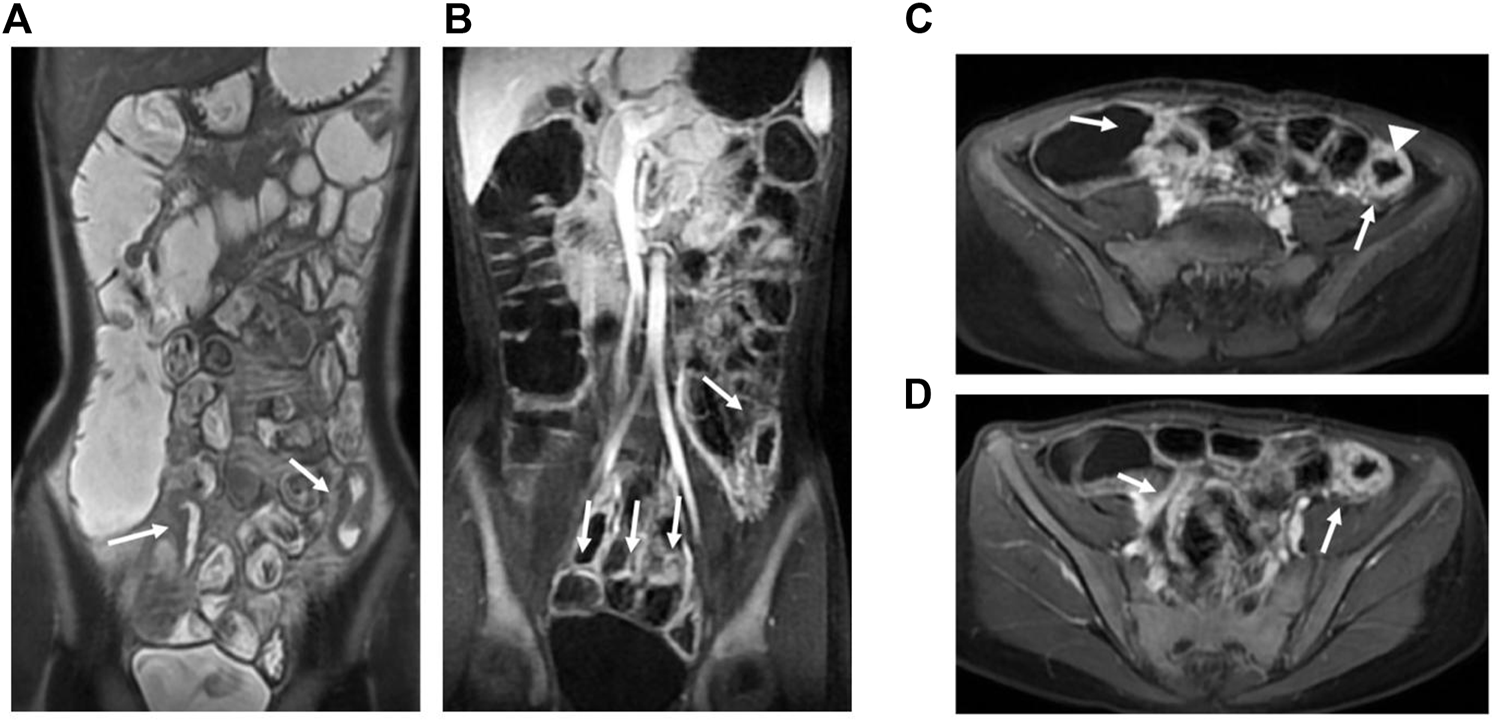

The median MaRIA score of the 82 subjects was 7.59 (2.24, 49.3). Figure 2 and Figure 3 show representative views of the MRE examination. According to the MaRIA classification, 36 patients were inactive or clinically insignificant (MaRIA<7), 11 exhibited mild activity (7 ≤ MaRIA<11), and 35 had moderate to severe activity (MaRIA≥11). Crohn’s disease activity determined by CECDAI and MaRIA were moderately correlated (r = 0.406, p < 0.05), and they were consistent (kappa = 0.299, p < 0.05) (Table 3). MaRIA and PCDAI were slightly correlated in determining the activity of CD (r = 0.254, p < 0.05), and they exhibited weak consistency (kappa = 0.135, p < 0.05) (Table 4). By multiple linear regression, the severity level of MaRIA was significantly and negatively correlated with ALB (r = -1.064, p < 0.05). However, it was not significantly correlated with CRP, ESR, HB, HCT, WBC, and PLT.

FIGURE 3. MRE image: Bowel wall thickening in the terminal ileum and the left hemicolon with increased mural signal intensity (arrow in A). Coronal (B) and axial (C,D): Asymmetric bowel wall thickening (arrow in B, C, and D). Luminal ulcerations (arrowhead in C).